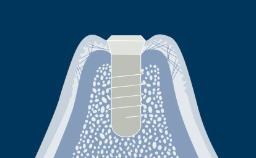

A osteotomia do implante é uma etapa cirúrgica essencial na implantodontia. Termina com a inserção de um implante dentário que posteriormente fornecerá ao paciente um substituto fixo ou removível para a ausência de dentes. Neste módulo, descreveremos primeiro a técnica correta de preparação óssea para a instalação do implante. Posteriormente, abordaremos os ajustes do protocolo necessários em diferentes densidades ósseas. Finalmente, discutiremos os riscos potenciais associados à técnicas inadequadas de osteotomia.

- definir a sequência, velocidade e técnica de perfuração e reconhecer sua relação com a estabilidade primária do implante e a osseointegração

- selecionar o procedimento de perfuração apropriado para determinados tipos ósseos